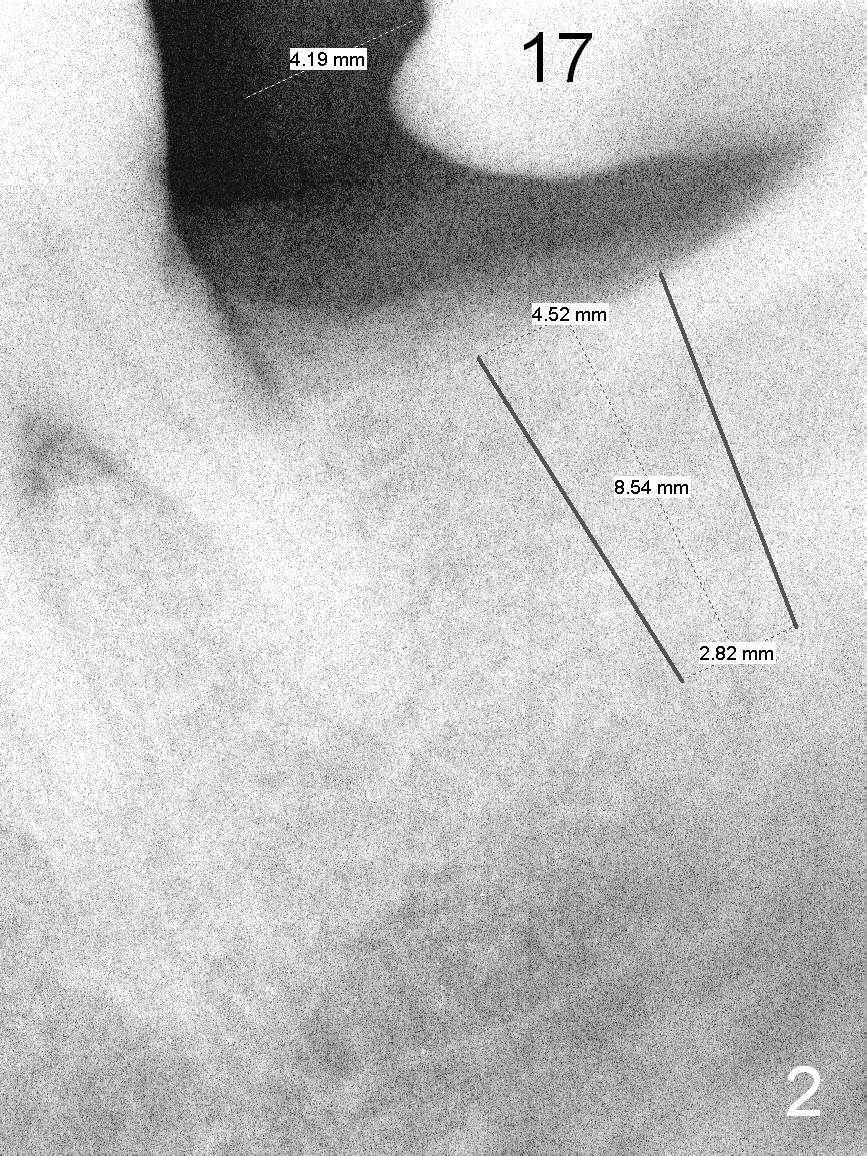

A 53-year-old lady has a small statue.  The tooth #18 was extracted due to #17 impaction (Fig.1).  To prevent further supraeruption of #15, an implant is to be placed at the site of #18 (Fig.2).  After use of a 4 mm implant spacer and starter and 8 mm pilot drills, insert a short parallel pin for occlusion check and a calibrated one for X-ray.  A relatively small and short implant will be sufficient for function.  Scaling & root planing and #17 extraction have been finished.